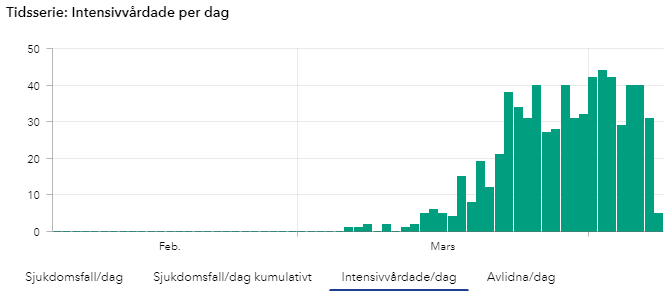

ICU [SWE]

New Covid-19 patients Being Treated at the ICU in Sweden.

(Number of COVID-19 cases over time in Sweden, updates during mornings at 14:00 so todays numbers are not yet complete until the next day).